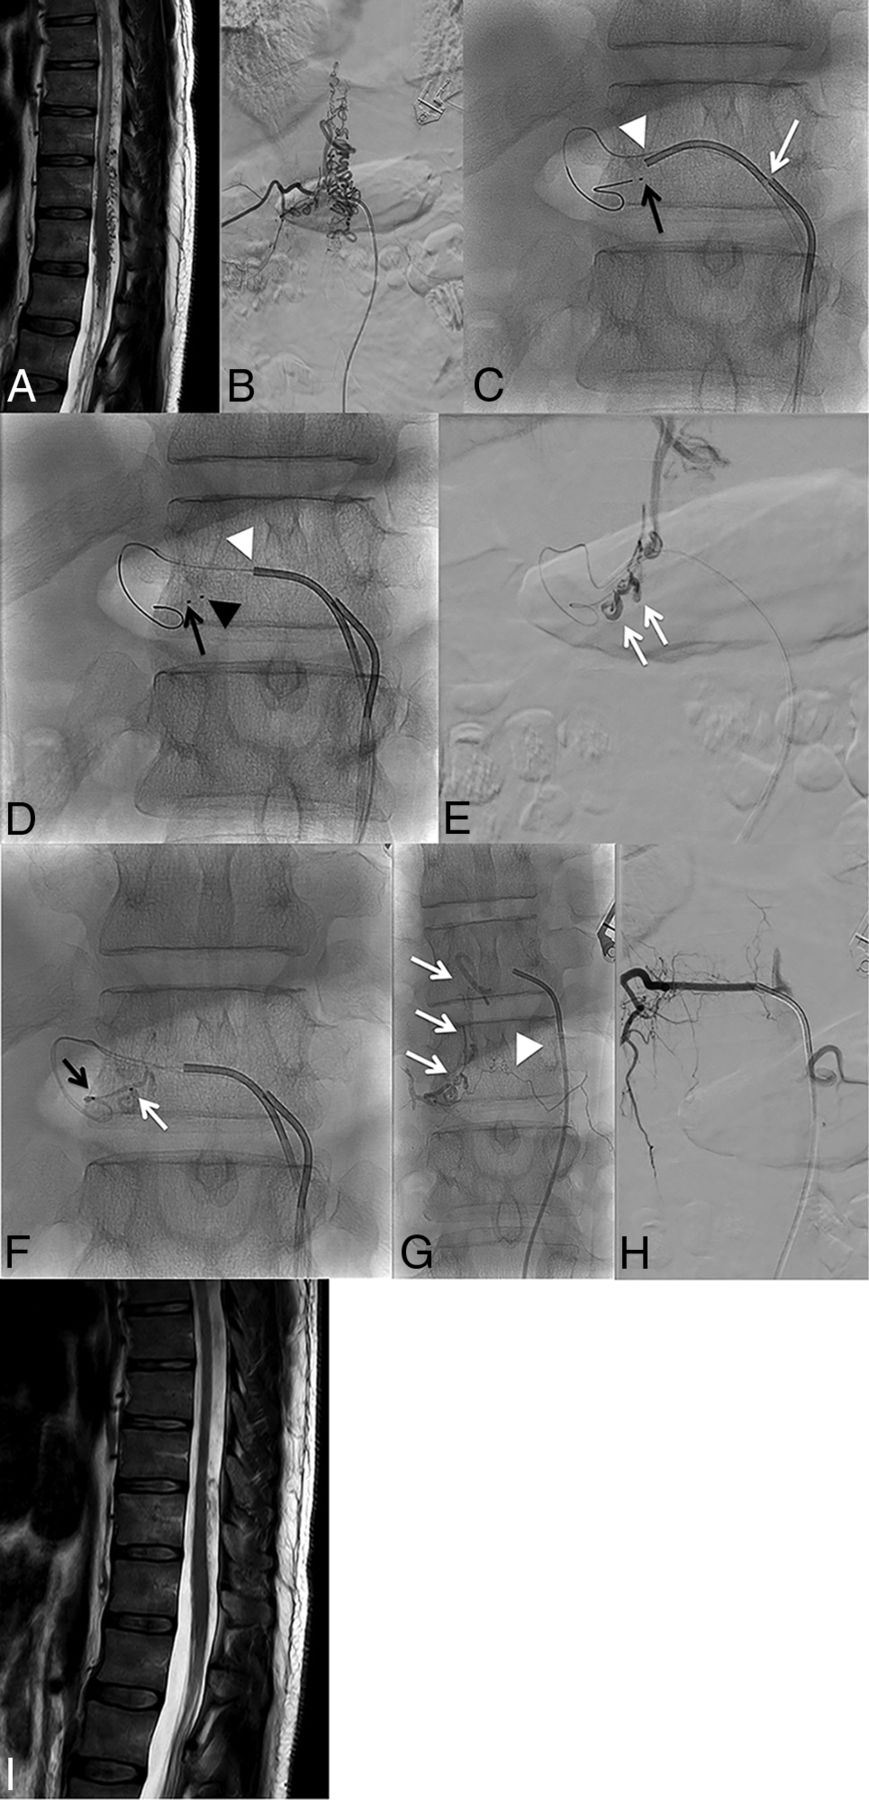

Patient in his or her 40’s presenting with lower limb paresthesia, constipation, and bladder disturbance lasting for 36 months. A, Spinal cord MR imaging. T2WI, sagittal section, shows the hyperintense signal of the spinal cord extending up to T8 and multiple flow void signals in the enlarged spinal veins. B, Spinal DSA. Right T11 angiogram in a postero-anterior projection shows a spinal arteriovenous fistula with both ascending and descending venous drainage. C, Navigation of the microcatheter No. 1 (dedicated to the PCT plug) (black arrow). Then, the guiding catheter No. 1 is disengaged from the right T11 intercostal artery (white arrow). The guiding catheter No. 2 is subsequently positioned at the ostium of the segmental artery (white arrowhead). D, Navigation of the second microcatheter (No. 2) (black arrowhead) from the guiding catheter No. 2 (white arrowhead) as close as possible to the shunt point. Note the tip of microcatheter No. 1, located proximal to the tip of microcatheter No. 2. E, Ultraselective angiogram in a postero-anterior projection from microcatheter No. 2. The origin of the main draining vein (radicular vein) is clearly seen (double white arrow). F, PCT. Injection of 50% n-BCA through microcatheter No. 1 to create the proximal plug (black arrow). Then, injection of a 20% dilution of n-BCA is performed to embolize the fistula (white arrow). G, Plain x-ray in a postero-anterior projection shows the glue cast. Note the filling of the origin of the radicular vein (white arrows) and also progression of the liquid embolic agent through the retrocorporeal anastomosis (white arrowhead). H, Right T11 angiogram at the end of the procedure shows complete occlusion of the fistula. I, Spinal cord MR imaging 14 months after embolization. T2WI, sagittal section, shows complete resolution of the spinal cord edema.